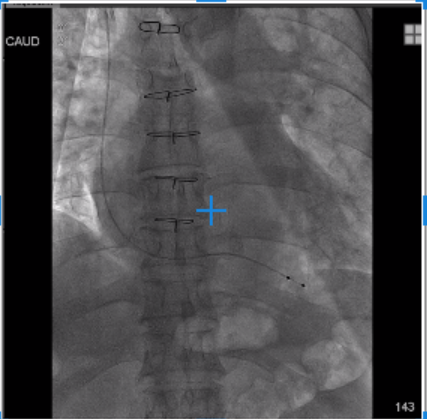

1.经颈静脉放置起搏电极

2.股静脉入路,超声指导下进行房间隔穿刺,冒烟及超声确认并将导丝置入左上肺静脉

3.可调弯鞘辅助跨瓣,左室送入预塑型加硬钢丝

4.使用12mm(12mm*40mm)小球囊预扩房间隔,球囊系统预跨二尖瓣生物瓣

5.通过预塑型加硬钢丝建立的轨道,将SAPIEN 3瓣膜反装并通过Commander输送系统送至外科生物瓣瓣环处

6.快速起搏下进行瓣膜释放

7.Tee观察无PVL且左向右分流,瓣中瓣植入后观察左房峰值压明显下降,二尖瓣平均跨瓣压差降至5mmHg。